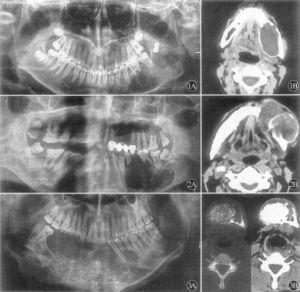

CT檢查1、X線檢查:X線攝片示頜骨膨隆,不規則多房性囊性透光影像,此影像邊緣不光滑,有半月狀切跡,分房大小懸殊,波及牙槽骨者可有明顯的“根尖浸潤征”--牙根尖的牙槽突骨質呈不規則的破壞與吸收,牙根可呈鋸齒狀或截斷樣吸收,如有迅速長大同時伴疼痛潰瘍等症狀,X線表現骨間隔破壞消失,呈斑點狀影時,應疑有惡性變。

高分辨螺鏇CT配合牙科軟體技術,特別是多層螺鏇CT的容積數據採集技術,不僅能夠重組出反映頜骨解剖特點的二維曲面圖像和任意方位上的二維圖像,而且能夠精細顯示病變的三維結構;由於CT有較高的密度解析度,還可顯示病變的內部結構和囊內容物的密度;此外,套用不同的窗技術,還可分別觀察骨,軟組織病變的細節,所有這些改善均有助於頜骨造釉細胞瘤特徵的顯示。

4.X線攝片示頜骨膨隆,不規則多房性囊性透光影像,此影像邊緣不光滑,有半月狀切跡,分房大小懸殊,波及牙槽骨者可有明顯的“根尖浸潤征”--牙根尖的牙槽突骨質呈不規則的破壞與吸收,牙根可呈鋸齒狀或截斷樣吸收。